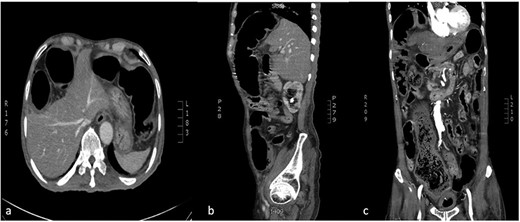

Chest X-Ray was unremarkable except for the visualized part of the abdomen that demonstrates distended bowel filled with gases (Fig. 1).

chest X-ray revealed visualized part of the abdomen demonstrate distended bowel filled with gases under the right hemidiaphragm.